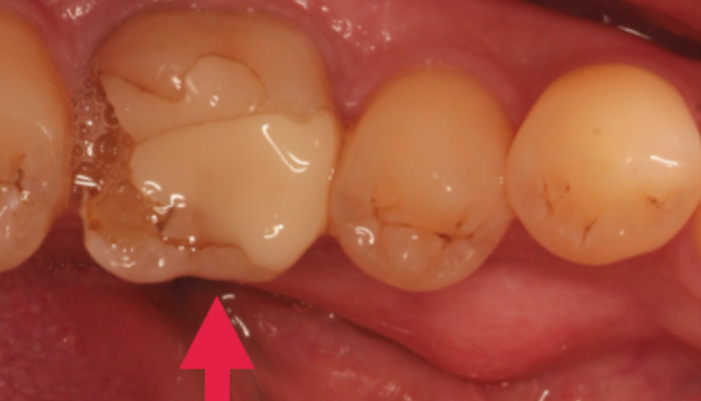

治療後

患者様は「他院で神経を取るしかないと言われたが、できれば神経を残したい」とのご希望で来院されました。初診時には冷たいものがしみる症状はありましたが、自発痛や打診痛はなく、診査の結果、歯髄を温存できる可能性があると判断しました。

治療では拡大視野下でむし歯の感染部分を正確に除去し、MTAを用いた歯髄温存療法を実施しました。

| 主訴 | 歯に穴が空いた |

|---|---|

| 治療期間 | 1ヶ月 |

| 治療費 | ¥33,000 |

| 治療内容 | むし歯が大きく、神経を残す治療(歯髄温存療法)を行い、神経を残しダイレクトボンディングにて修復しました。 |

| 治療のリスク | 治療後に痛みが出ることがあります。また、痛みが強くでる場合は神経を取る治療に移行することもあります。 |